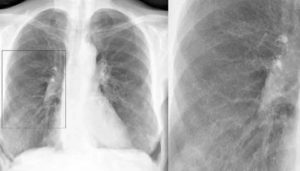

Простой острый бронхит увидеть на рентгеновском снимке невозможно, визуализации поддаются только обструктивные и хронические длительно текущие формы заболевания. Рассмотрим примеры того, как выглядит бронхит на рентгеновских снимках:

На фото 1 и 2 видно, как выглядит бронхит на рентгеновских снимках, а точнее, признаками заболевания являются:

- изменение размера и структуры корней легких,

- нечеткость его контуров,

- изменение легочного рисунка (как правило, усиление),

- утолщение стенок бронхов при хроническом бронхите (симптом «трамвайные рельсы» фото 3).

Важно! На обычном рентгеновском снимке легких можно рассмотреть только трахею и крупные бронхи, мелкие бронхи не видны.

Еще одной особенностью бронхита является диффузность поражения, то есть вовлечение в процесс обоих легких.